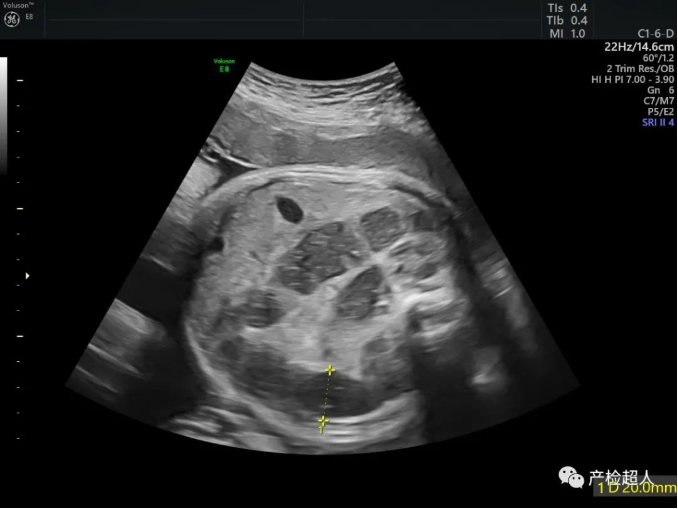

37周,腹腔及肛门附近图像如下,您作何考虑,欢迎留言,下期答案揭晓。